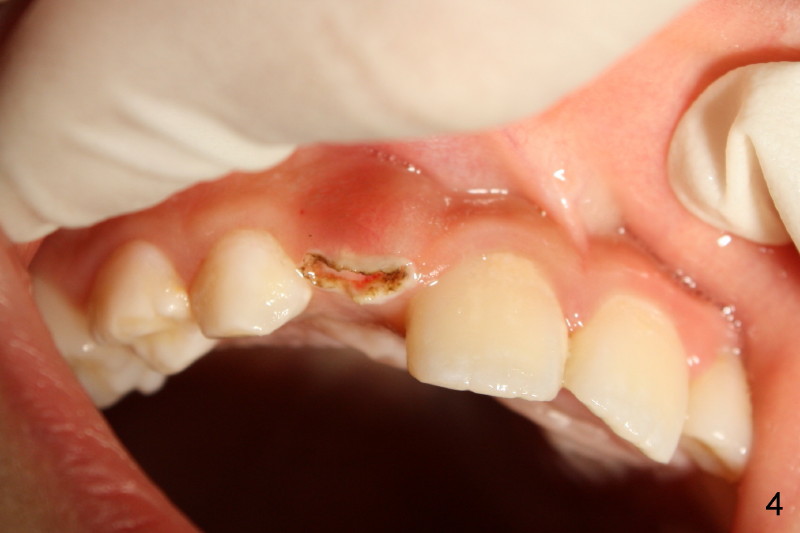

Panramic X-ray was taken when Edward was 6 years 5 months old (Fig.1). His parents and he himself found that the upper right lateral did not erupt at the age of 9 years 2 months (Fig.2-4: *). Gingivectomy was performed using soft tissue laser to expose the incisal edge of the lateral. Five months later, the lateral has erupted partially (Fig.5-8), but the family is concerned about the cosmetic issue. It appears that the upper midline has shifted to the right (Fig.6). Periapical film is planned to take to confirm the relationship between the canine and the lateral.